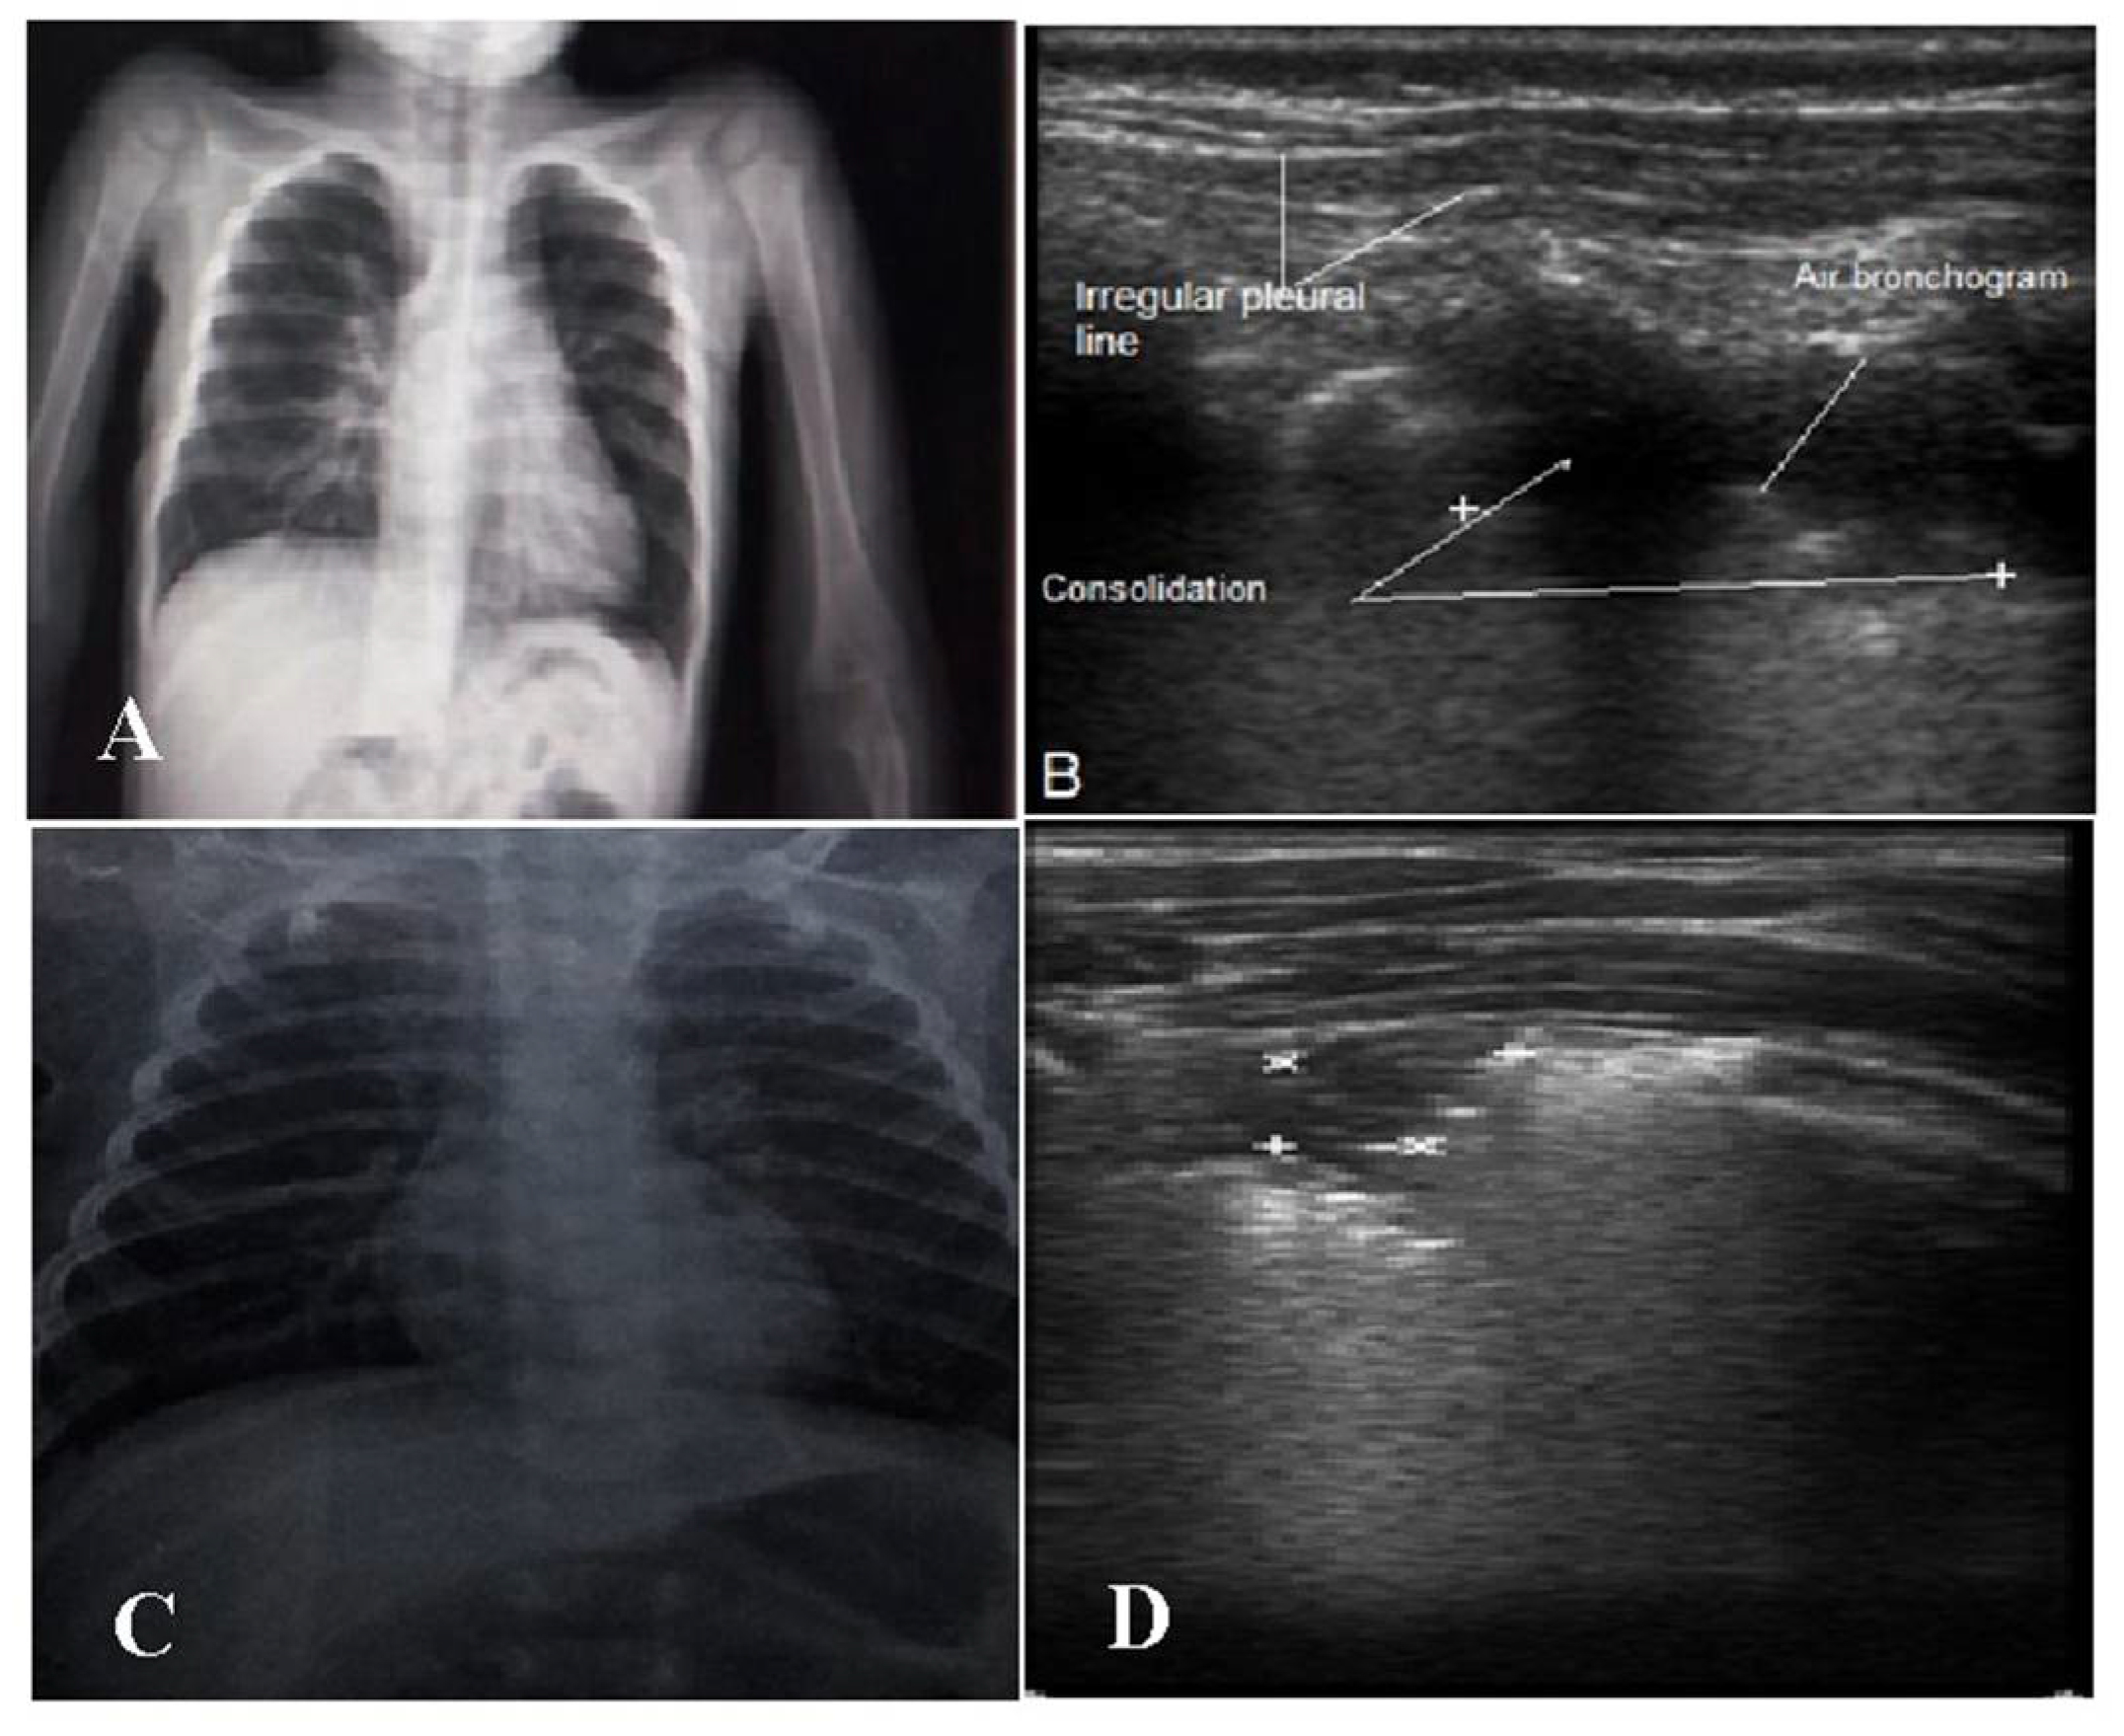

| CXR Findings | ||||

| Increased bronchovascular markings | 6 (17.6%) | 8 (38.8%) | 0.04 * | |

| Consolidation | Present | 24 (70.5%) | 4 (22.2%) | 0.002 * |

| Absent | 10 (29.5%) | 14 (77.8%) | ||

| Reticulonodular opacities | 0 (0%) | 8 (38.8%) | 0.02 * | |

| Air bronchogram | 11 (32.3%) | 2 (11.1%) | 0.17 | |

| LUS Findings | ||||

| Pleural line | Regular | 7 (20.5%) | 11 (61.2%) | 0.009 * |

| Disturbed | 27 (79.5%) | 7 (38.8%) | ||

| Subpleural consolidation | >1 cm | 30 (88.2%) | 4 (22.2%) | <0.0001 * |

| <1 cm | 4 (11.8%) | 14 (77.8%) | ||

| Air bronchogram | Yes | 30 (88.2%) | 1 (5.5%) | <0.0001 * |

| No | 4 (11.8%) | 17 (94.4%) | ||

| B-lines | Yes | 4 (11.8%) | 15 (83.8%) | <0.0001 * |

| No | 30 (88.2%) | 3 (16.2%) | ||

| Lung sliding | Normal | 8 (23.5%) | 16 (88.8%) | <0.0001 * |

| Decreased | 26 (76.4%) | 2 (11.2%) | ||